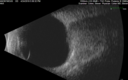

63 year old female She noticed a new thumbprint on her right eye with decreased vision March 10, 2019.  She waited a few days.  She was an eye institute where they said it was a cataract and scheduled for surgery.  She asked why if the cataracts are the same there was trouble with the one eye. He agreed and sent her to his retina specialist who noticed a problem and suggested a referral out. She has no health problems otherwise but has not been to a doctor lately.   VA OD: Dcc20/125 PHNI Ncc20/400 VA OS: Dcc20/50 PH20/32 NccJ5 IOP: TP: OD:23 OS:22 Time:15:56

Lung Cancer Metastasis to Right Eye372 views63 year old female with vision loss for 6 weeks. She had been scheduled for cataract surgery and then a tumor was found. She was ultimately diagnosed with lung cancer. Vision is 20/10000000